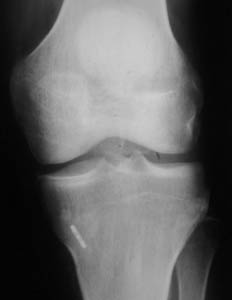

Figura 2B: Radiografía Rodilla de Frente donde podemos observar el Retrobuttom anclado en la cortical tibial